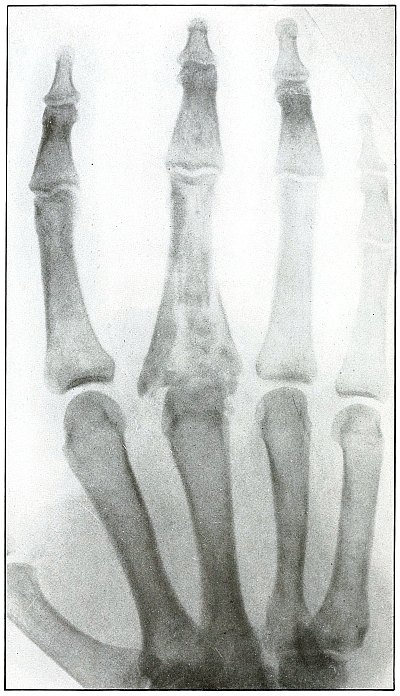

Plate 43.

_

[Pg 97]

Rifle—Plate 43.

UPPER EXTREMITY.

Gunshot Fracture of the Metacarpus.

Wound of entrance, inner aspect of the hand over proximal end of the fifth metacarpal.

Wound of exit, on the outer border of the hand over the distal end of the second metacarpal.

The velocity of the bullet was in mid or long range, as it displaced no fragments, and as it made a point of entrance and exit about the same in appearance.

The wound was infected, which is more frequently the case in the hand than in the forearm.

The treatment is conservative with free incision and drainage in the management of infection. [Pg 98]